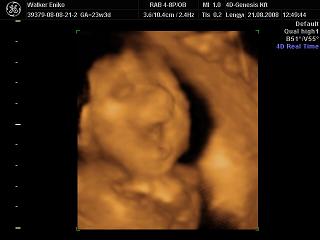

Nagyon helyesek a 4D-s fotók!!!